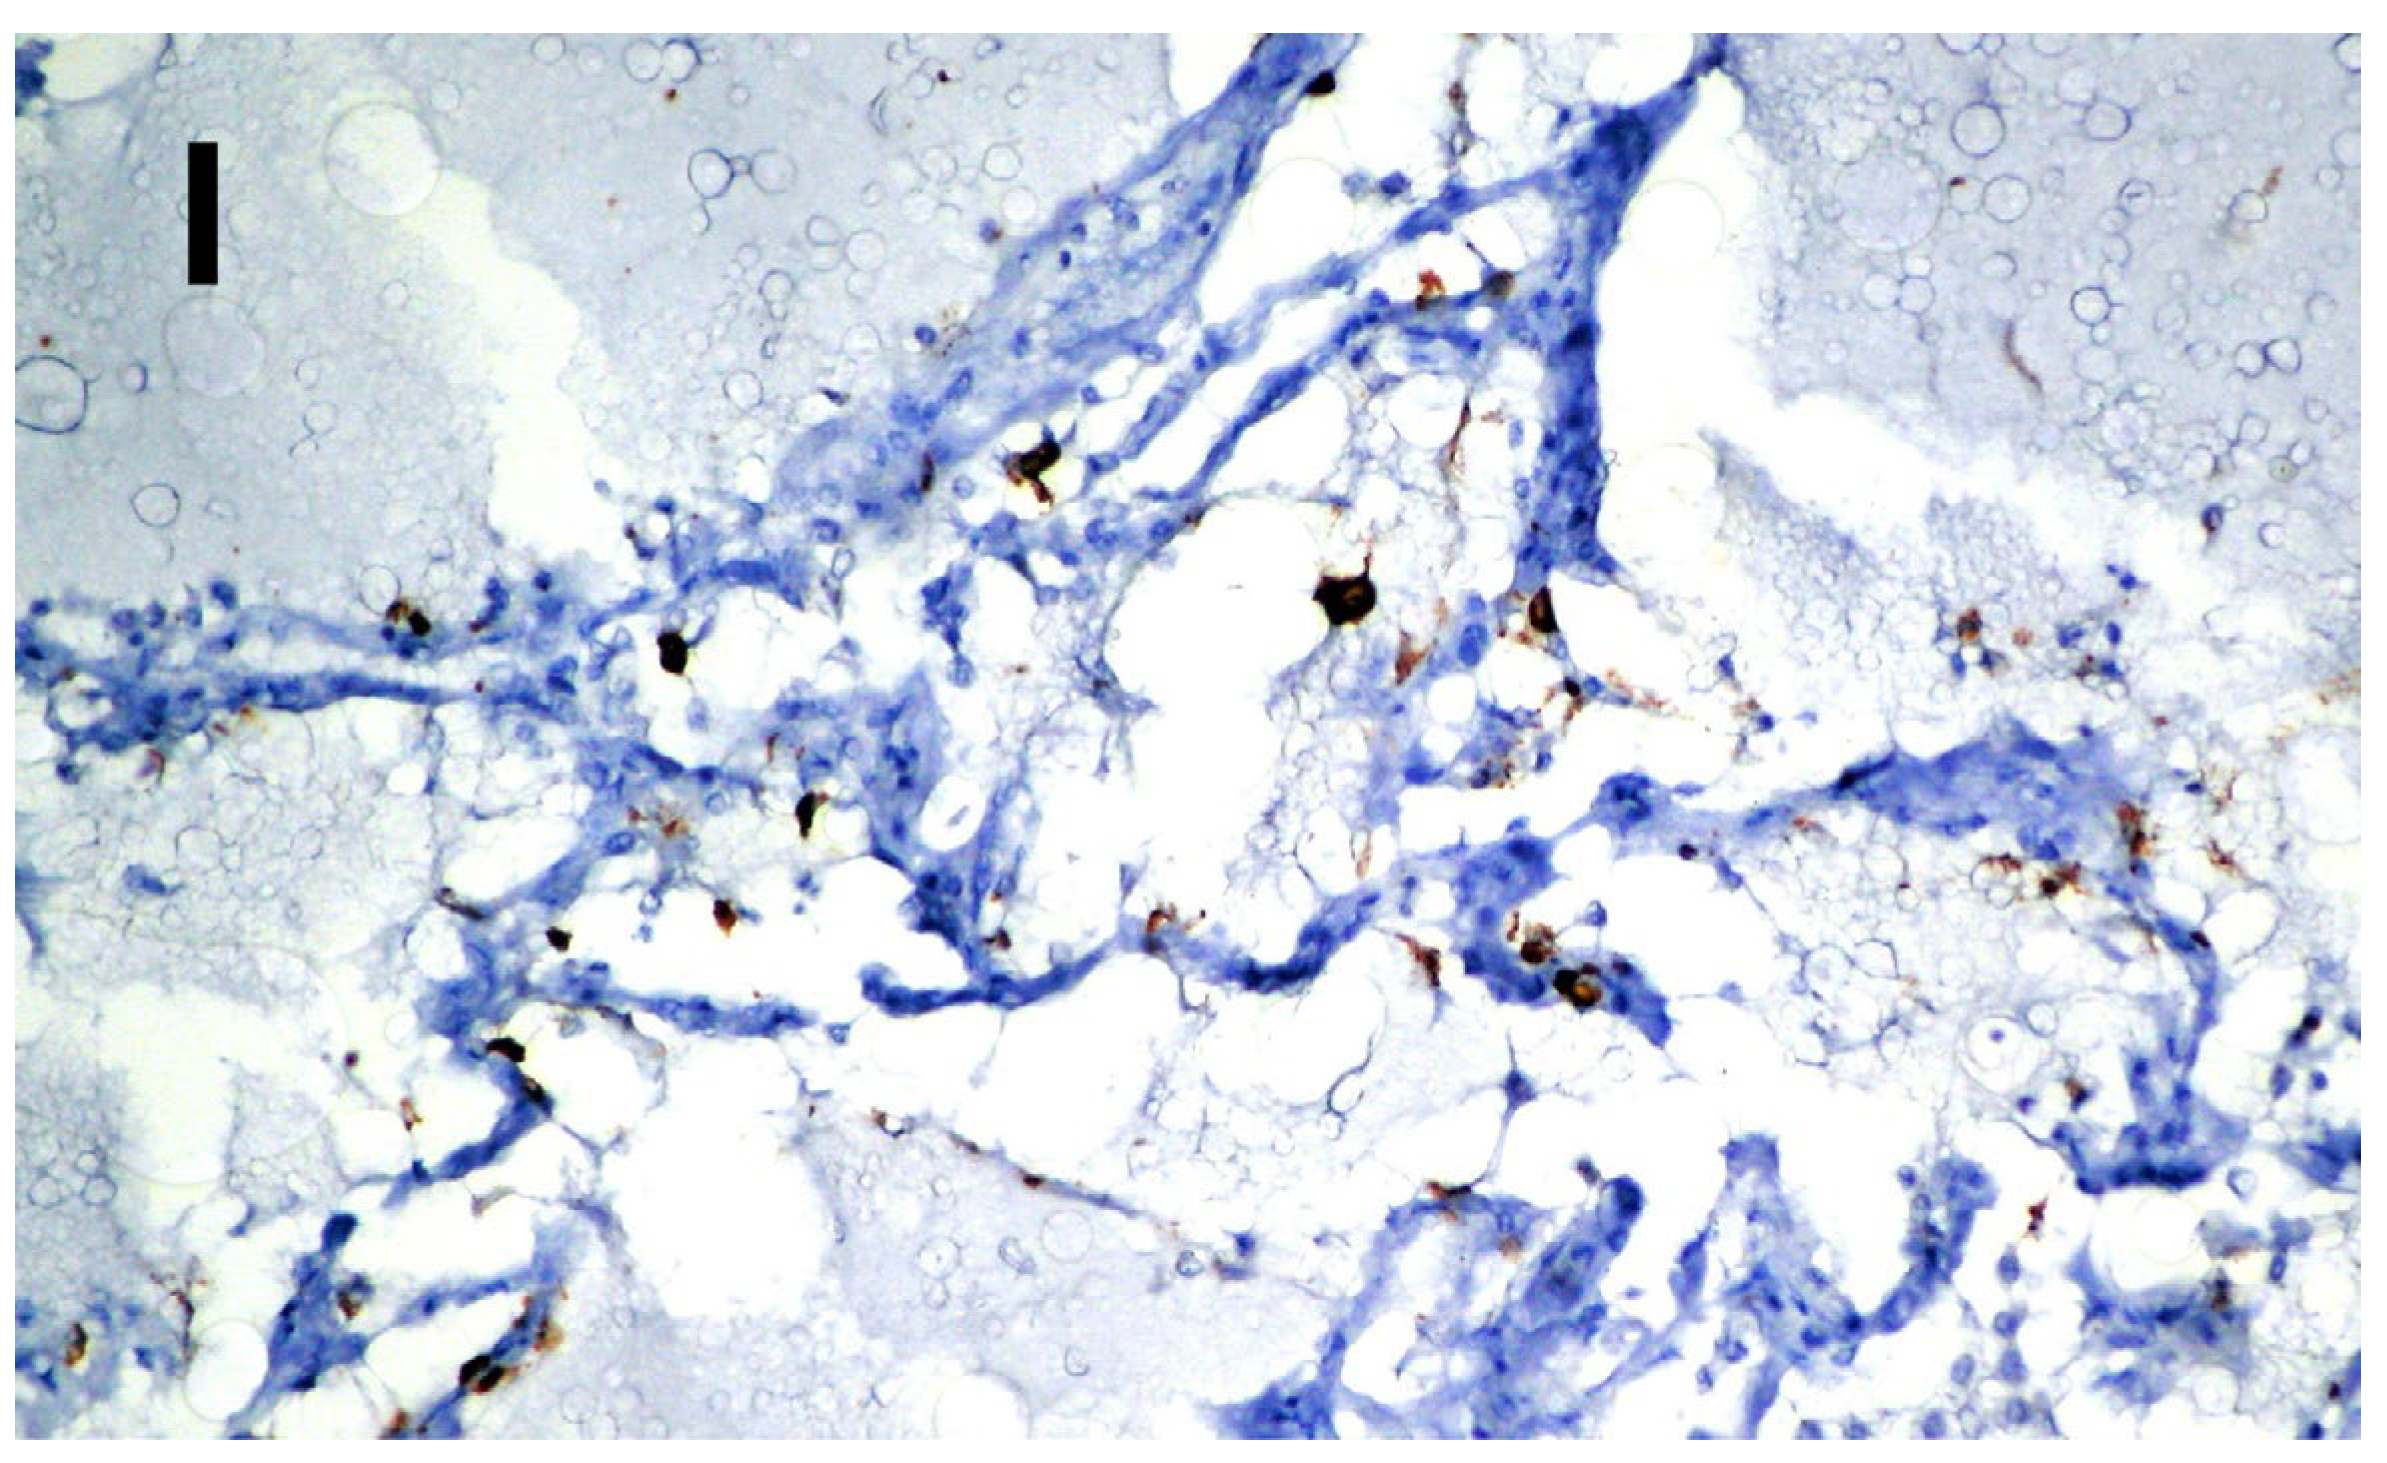

| Lung | Positive on the vascular endothelium (Figure 3G) | Positive on alveolocytes (Figure 3I) |

| Spleen | Positive on the lymphocytes in the follicles (Figure 3H) | Negative |